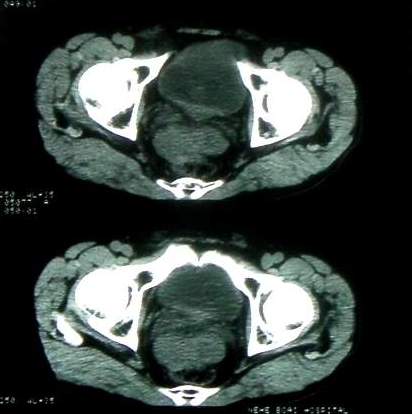

男 60岁,下腹部肿块半年余

前列腺肥大,密度不均。伴盆腔实性肿块。考虑前列腺癌伴盆腔转移。建议增强扫描。

考虑来源于肠道的肿瘤,乙状结肠?询问排便情况

盆腔恶性占位,间质瘤可能性大

乙状结肠间质瘤

盆腔恶性占位,间质瘤可能性大。

病理结果:肠系膜肉瘤

病灶形态不规则,偏心性裂隙样坏死,支持恶性病变。来源不好定。感谢反馈结果--肠系膜肉瘤。